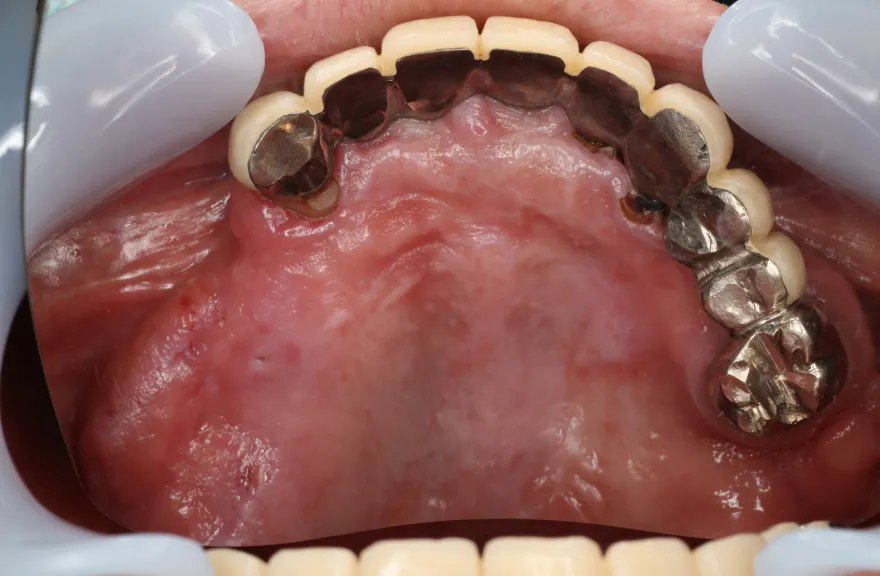

右上の奥歯が取れたということで来院されました。

各所の金属は昔に治療されたもので、外してみるとどれも虫歯になっていました。

一つずつ虫歯治療を行い、インプラント治療、矯正治療を並行して行いました。 - 治療費用・方針

写真の通りに治療を終了いたしました。

各所虫歯に侵食されていましたが、歯を残すことができたのでインプラントの数をおさえることができました。

下の前歯が先天的に1本欠損しており、そのため噛み合わせを構築することが難しいケースでした。矯正治療を併用することで前歯と奥歯をバランスよく噛ませることに成功しました。